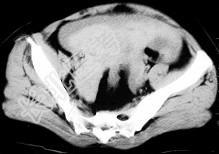

- 单项选择题女,32岁, 因停经46天,突发腹痛1天入院, 后穹隆穿刺抽出不凝血,CT检查如图所示, 下列说法错误的是 ( )

A、在左附件区可见一椭圆形略高密度病灶

B、病灶外缘较光整

C、盆腔内较高密度积液

D、此为宫外孕

E、此为卵巢巧克力囊肿